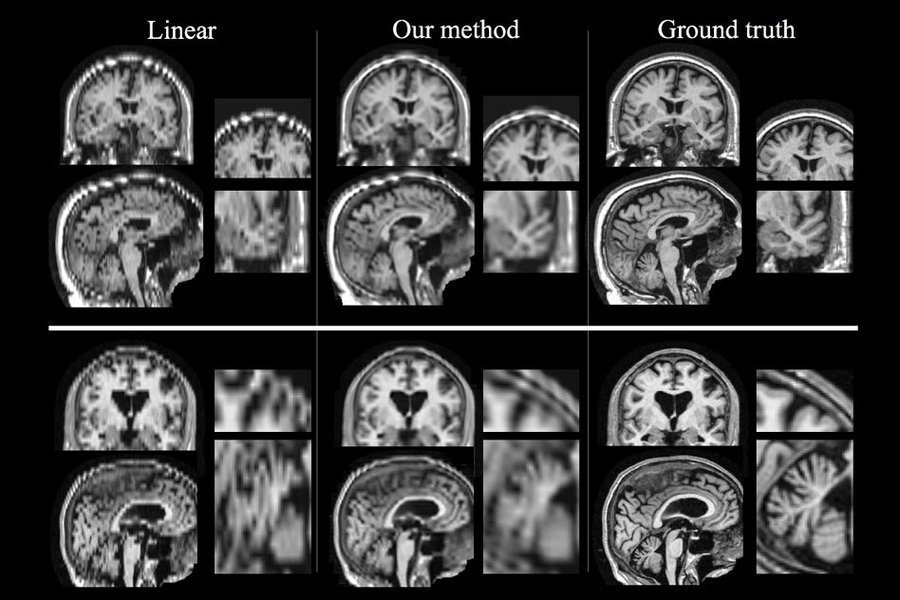

New technique makes brain scans better, MIT News